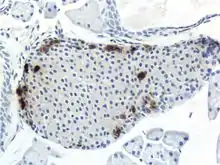

Pancreatic polypeptide is synthesised and secreted by PP cells (also known as gamma cells or F cells) of the pancreatic islets of the pancreas.[3][4] These are found predominantly in the head of the pancreas.